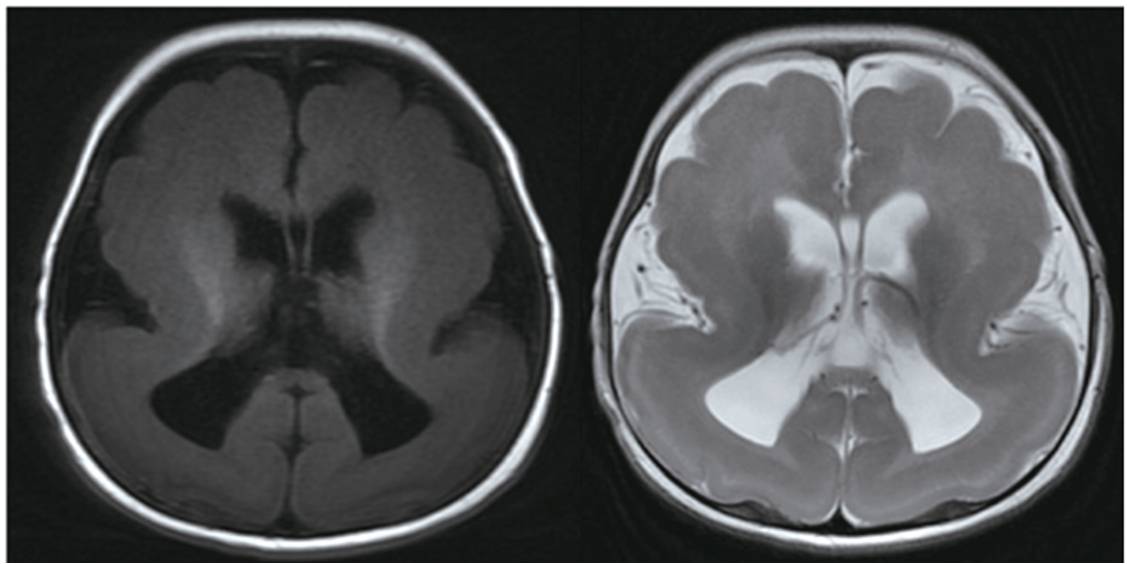

(三) 無腦回畸形 巨腦回畸形 多微腦回畸形

無腦回畸形也稱光滑腦,屬于神經(jīng)元移行異常疾病。發(fā)生在妊娠第8~14周。正常情況下先移動的神經(jīng)元構(gòu)成深部的皮質(zhì),而后來移動的神經(jīng)元需穿越先期移行的神經(jīng)元形成淺表的皮質(zhì),若后期移行的神經(jīng)元不能穿越先期移行的神經(jīng)元就形成無腦回或巨腦回畸形。

女,5月齡,巨腦回畸形。反復(fù)發(fā)作性抽搐。

在胚胎5~6月時,最后的神經(jīng)元移行波到達(dá)皮層表面時,如果出現(xiàn)異常,不能進行正常的分布,則引起新皮層內(nèi)細(xì)胞分布紊亂,生長不均勻,導(dǎo)致多微腦回畸形。

女,25歲,右側(cè)枕葉多微腦回畸形,白質(zhì)減少,右側(cè)側(cè)腦室后角不規(guī)則形擴大;頭顱不對稱,右側(cè)發(fā)育小。